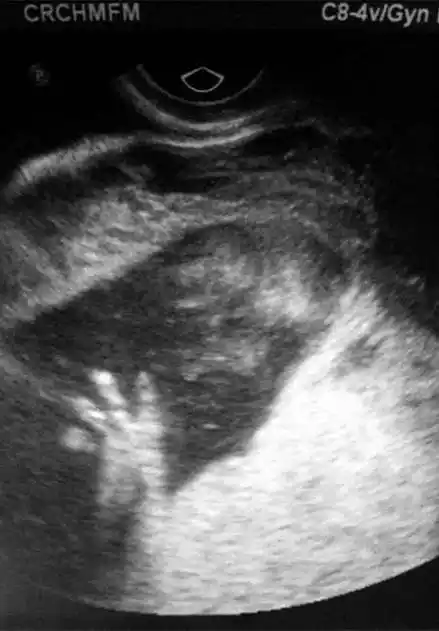

4) 早期堕胎:10周大的胎儿 向左转 向右转

孕龄到了这个月别轻易打掉ta,14周胎儿的实拍图,愿你能善良